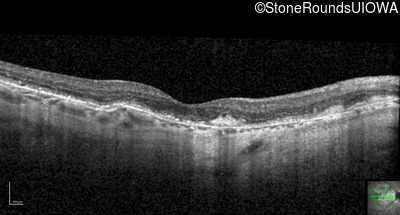

Optical Coherence Tomography - Right - 20/20 -2

Exemplar / OCT Stack

OCT Stack